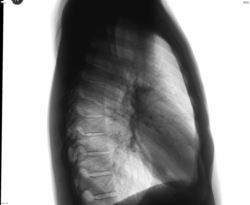

Справа в с\отд. в проекции 5 ребра есть какоето сгущение рисунка.Может из-за разворотоа не большого или суммация?

Согласен, возможно где-то сосуды сплелись меж собой в разговор. Но если допустить, что всё так и должно быть (внутри у него), не цепляет глаз больше на снимках ничего?

Мой не очень тонкий глаз зацепился за одну тенюшку, выбивающуюся из общей гармонии сосудистого переплетения. Но на боковой её не вижу.На дисковидный ателектаз похоже.

Цепляет верхушка справа.

Архива нет. Пациент молодой юноша. Много курит. Кашляет. Бабушка решила посмотреть, чтобы не было кроме бронхита в лёгких чего похуже.

Во всю спину у него, от шеи до поясницы, есть... графическое произведение всех цветов радуги. Красиво. Такое не каждому даже приснится. При просмотре снимка показалось избыточной точечности многовато. Задумался,.. чернила видны на снимке или просто уплотнены структуры лёгких, оттого что курилка. Может, чутка не того углядел. Если так, прошу извинить. Не хотел вносить очередной качественный беспредел.)